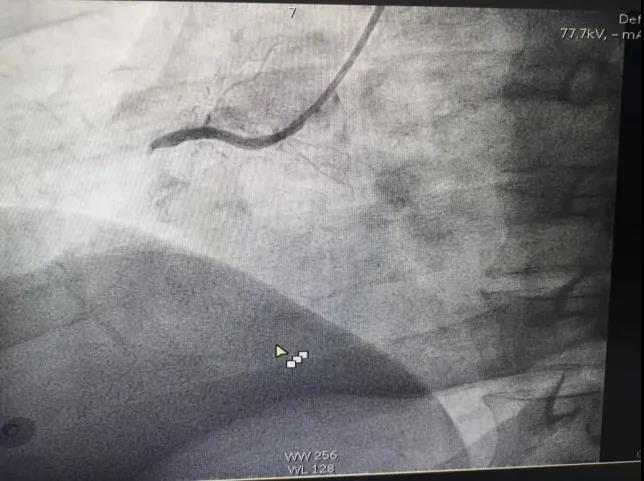

M老师在昏迷中,在各种仪器设备的强力生命支持条件下,由心血管介入团队对其完成了急诊冠脉造影检查——心脏右侧冠状动脉完全堵塞,伴有大量血栓形成。这是急性心肌梗死,需要马上手术开通血管。

堵塞的血管

心脏介入手术持续了差不多一个小时,从M老师一根堵塞的血管中抽出了大量新鲜血栓,并在严重狭窄的部位植入了两枚支架,整个血管恢复了良好的血流。